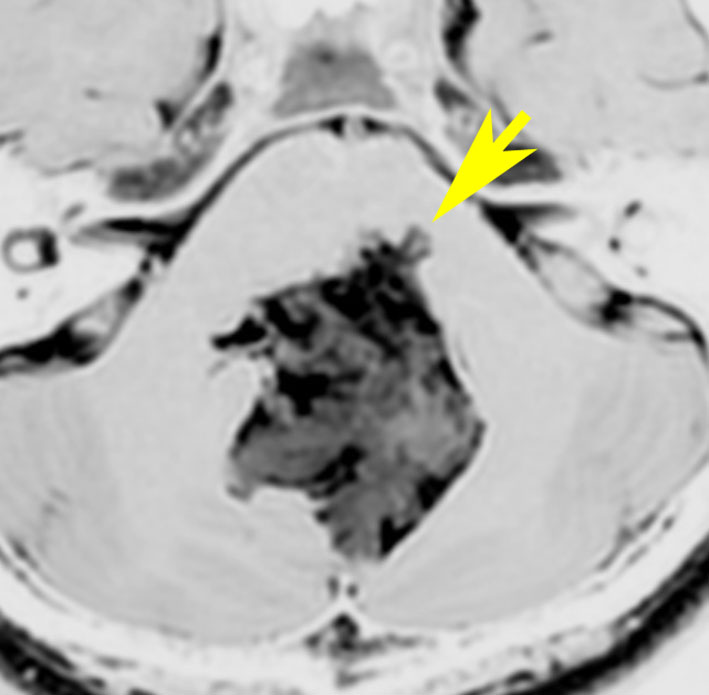

10代で発見された四丘体槽の類表皮のう胞です。左の画像,拡散強調像 DWIで真っ白に見えるので診断できます。真ん中は発見された時のもの,右側の画像は7年後です。ゆっくり増大してきたので,開頭手術(経テント法)で完全摘出しました。周囲の血管や神経に癒着するのでそれほど簡単な手術ではありません。